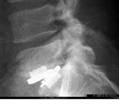

foto via de abordaje

https://espaldaycuello.com/atrodesis-intersomatica-lumbar-anterior-alif/